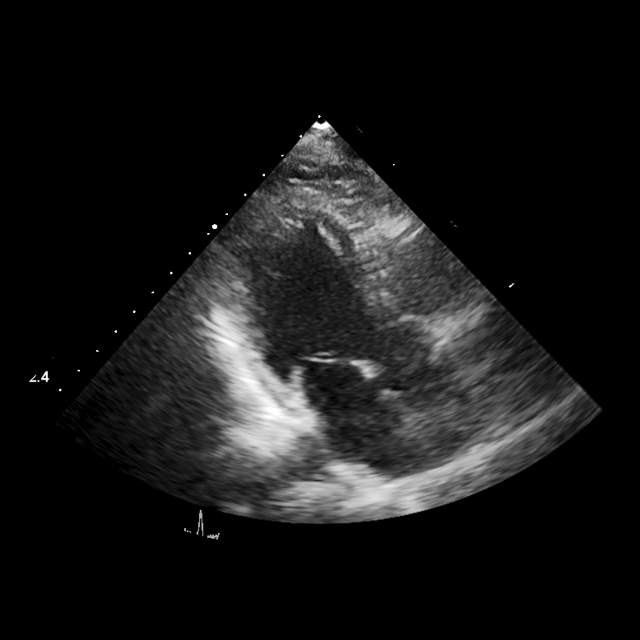

TTE is widely used in cardiology for the diagnosis and follow up of patients affected by cardiovascular disease. Echo studies obtained from TTE examinations cover a wide range of views, resulting in large datasets to be reviewed by clinicians. AI-based models for TTE view classification can prove beneficial in identifying clips of desired views or generating structured reports. For this task, we use an internal multi-vendor dataset, including a wide range of transducers, spatial and temporal resolutions, image quality, imaging depth, color doppler and the use of contrast. A total of 18 different TTE views are covered in the datasets, including standard views and those where contrast is used. All the images were labeled by echocardiographers following the recommended guidelines [Mitchell2019GuidelinesFP].

The model architecture for this task is based on our pretrained EchoApex backbone and a linear classification layer, which uses the features from the classification (CLS) token to produce the logits, following Fig. 3. We use a weighted cross-entropy loss to account for class imbalance. The distribution of the classes in our dataset, sample images from the various classes and the list of hyperparameters for this experiment are given in the Supplementary Fig. 7, 8 and Table. 2, respectively.

When testing our model, we extract 5 frames from each video sequence, classify them individually and apply majority voting to obtain a sequence label. We found this strategy to be more effective in reducing confusion. Indeed, using multiple frames can help with ambiguity between views due to the cardiac motion during the cardiac cycle, e.g. between the apical four and five chamber views. The confusion matrix in Fig. 3 details the results of the best performing EchoApex model with a ViT-B backbone (EchoApex-B) over the 18 classes. The confusion between the parasternal long axis left ventricle (PLAX LV), increased depth (PLAX ID), and zoomed on the mitral and/or aortic valves (PLAX Valves) is due to the same structures being present in the three views, with the main difference between them being the varying zoom levels. Finally, the A3C and the PLAX ID/LV views exhibit the same anatomical structures but the angulation differs between the two sets of views. The model tends to make errors when the image quality is poor or the angulation not adequate.